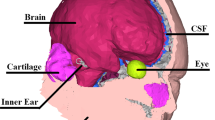

Skin flaps containing muscle and periosteum of the skull midline points and left mastoid were made an incision to measure the vibrations directly from the bone. The seven points are as follows: (1) the chin point of the mandibular bone, (2) the nasion point of the nasal bone, (3) the forehead point of the frontal bone, (4) the upper-forehead point near the frontal-parietal bone suture, (5) upper and upper-forehead point of the parietal bone, (6) top point near the parietal-occipital bone suture, and (7) occipital point of the occipital bone. The detailed description of measurement position is shown in Supplemental Fig. 1.

Five triaxial accelerometers were used during this experiment (No. 1 to 4, Brüel & Kjær Type 4524B; No. 5, Brüel & Kjær Type 4535B). The 4525B is a 10 mm cube weighing 4.4 g and the 4535B is a 12 mm cube weighing 6 g. To minimize any structural changes to the skull, all accelerometers were attached to the measurement sites using a liquid superglue without the need for drilling or inserting needles. The bone vibrator was secured to the right mastoid using a steel headband with a static force of 5.5 N. Triaxial accelerometer No.1 was attached on top of the bone vibrator, while No. 5 was attached to the left mastoid. Furthermore, three triaxial accelerometers, No. 2, 3, and 4, were attached side by side on the point of the skull’s midline and moved to 7 different locations, ranging from the chin to the occipital, to observe the complex modal behavior and dominant pathway at the midline. In other words, while No.1 and No.5 were kept fixed, No. 2, 3, and 4 were moved in one set from one location to the next after the measurement was completed.

The measurement system employed two different coordinate systems: one for the mastoid positions and the other for the accelerometer positions at the midline. For the mastoid positions, the triaxial accelerometers (No. 1 and 5) were used to measure vibrations in three orthogonal axes—X-, Y-, and Z-axes. When triaxial accelerometers move along the midline (No. 2–4), the curvature of the head causes a misalignment between the accelerometer coordinates and the position of the vibrator or mastoid. To resolve this issue, the X-, Y-, and Z-axes of the triaxial accelerometers at the midline were redefined based on the sound propagation direction, using the elevation, azimuth, and normal directions. The elevation direction represents the direction of the top of the head, while the azimuth direction represents the contralateral direction from the right to the left ear. The normal direction is the line perpendicular to the tangent plane of the elevation, and the azimuth direction is the outer-right plane. The elevation and azimuth directions are longitudinal components propagating along the tangential plane, and the normal direction is the bending wave component.